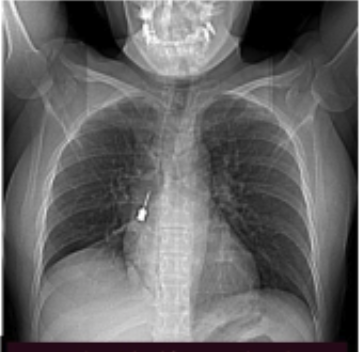

Le foto del cacciavite

In un comunicato, l’ospedale ha diffuso le foto del cacciavite incastrato, che ha richiesto l’operazione chirurgica per la donna. Dalla struttura sanitaria massimo riserbo su come sia stato possibile che quello strumento fosse finito in quel punto del corpo.